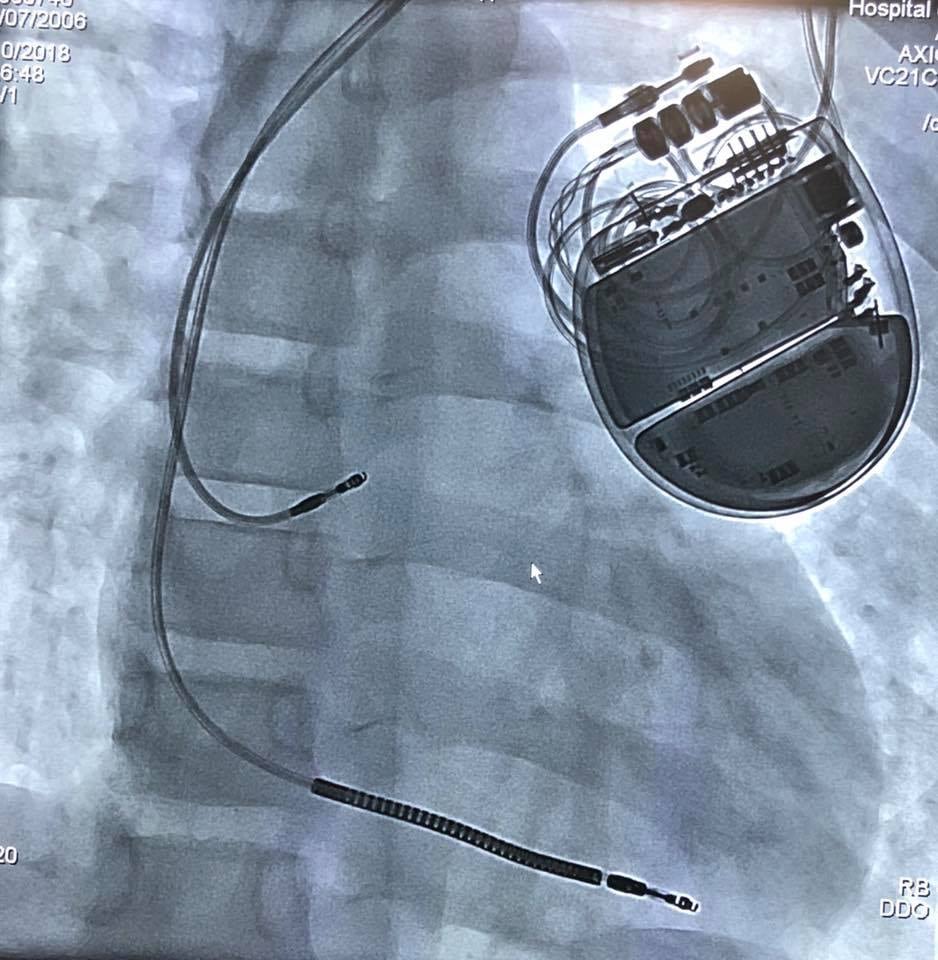

La solución no podía hacerse esperar. Cuando el menor estuvo estable y bajo control, con latidos del corazón constantes, fue trasladado en ambulancia hasta el HNN, donde ya sabían los pasos por seguir: la colocación de un dispositivo llamado implante desfibrilador automático, que es capaz de “leer” cuando el menor tiene un ritmo irregular en el corazón y envía descargas eléctricas hasta regularlo.

Este implante nunca había sido colocado en el país, dado que son pacientes sumamente específicos los que pueden necesitarlo.

La parte más difícil del procedimiento no es la colocación del implante, pues este se coloca de manera muy similar a como se hace con un marcapasos. Lo realmente trascendental es programar el aparato para que sepa cuáles son las condiciones “normales” y a partir de cuáles debe descargar y con qué magnitud.

Una vez que el implante fue programado se le colocó al menor. El procedimiento fue realizado el miércoles pasado entre 8:30 a. m. y mediodía.